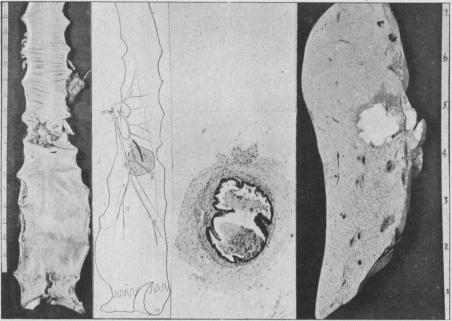

The Surgical Pathology of Rectal Cancer: President's Address.

Proc R Soc Med. 1944 Feb;37(4):131-44. doi: 10.1177/003591574403700402.